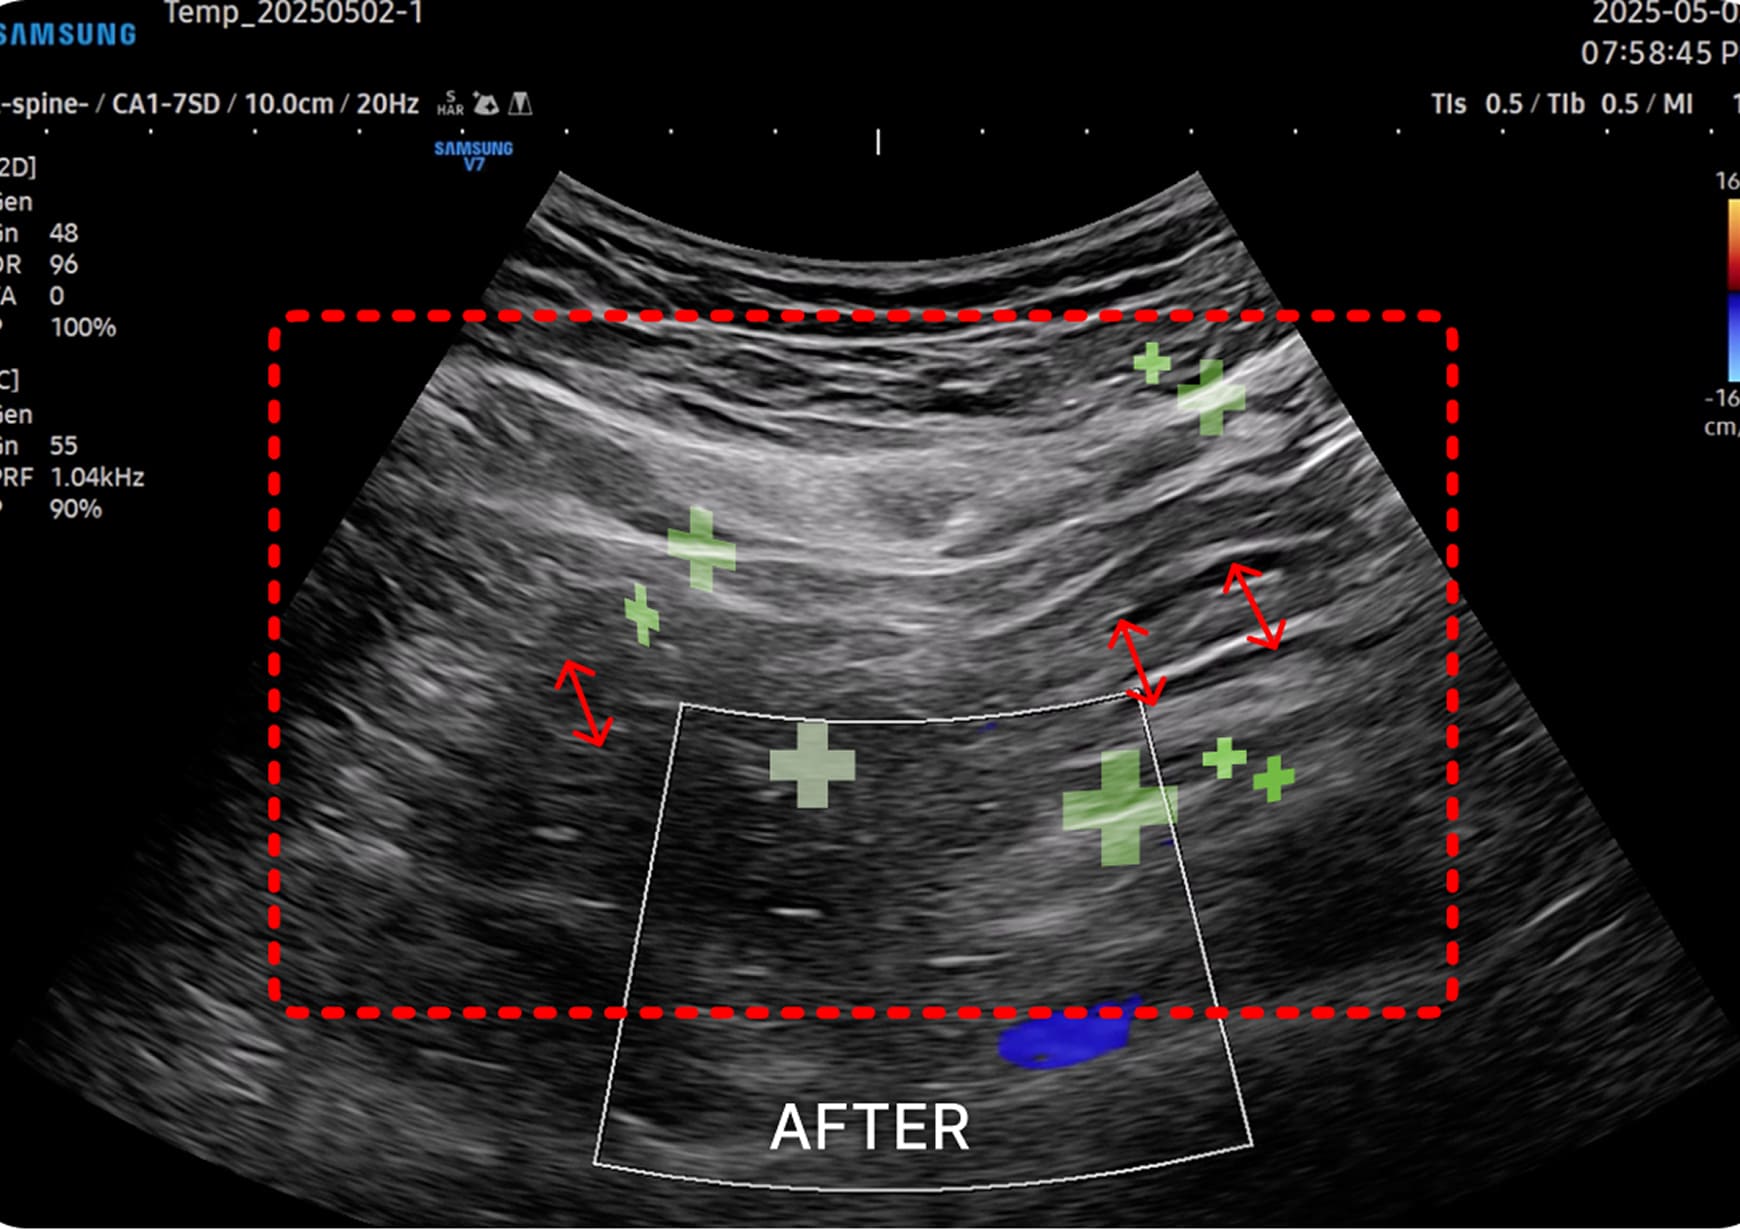

초음파 검사

1. 초음파 시술

초음파를 활용하여 근육과 신경 문제를

정확히 진단하고 치료하여 통증과 기능

이상을 개선하는 시술입니다.

미주신경

심장 박동을 감소하고, 위산 분비 및 위장관 운동 촉진

면역 반응 조절을 활성화하여 소화 기능을 강화합니다.

복강신경총

췌장, 위, 십이지장 등의 복부 장기의 허혈성 상태를 개선합니다.